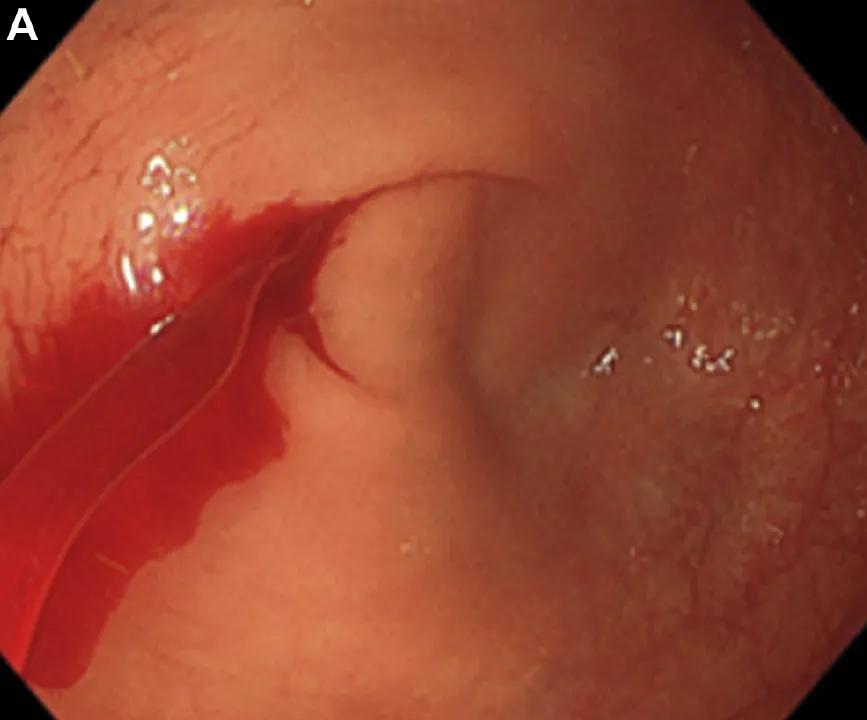

检查过程中可见整个结直肠肠和回肠末端均充满血液,根据颜色可判断,来自盲肠的血最新鲜。医生对肠道进行了灌洗,发现血液来源于阑尾上的一个小孔(图A)。

正确答案是D,具体为阑尾Dieulafoy病。